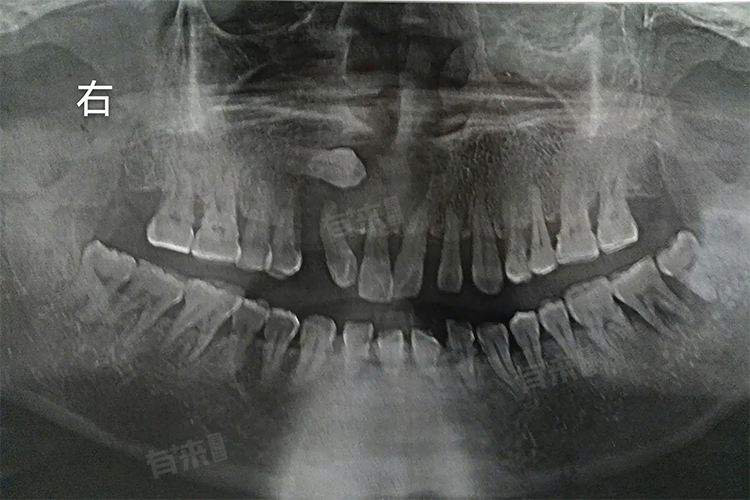

1、定期口腔检查:定期前往口腔科检查,通过X光片等影像学手段,观察埋伏牙状态。建议每年至少检查一次,及时发现其对周围组织的影响,以便医生根据情况调整观察或治疗方案。